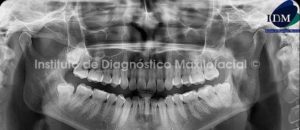

Paciente del sexo femenino de 58 años de edad, es referido a la consulta para evaluar la colocación de un implante dental en la zona de la pieza 1.5.